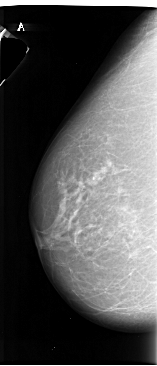

A_1012_1.LEFT_CC

LEFT_CC LINES 6571 PIXELS_PER_LINE 2821 BITS_PER_PIXEL 16 RESOLUTION 42 NON_OVERLAY